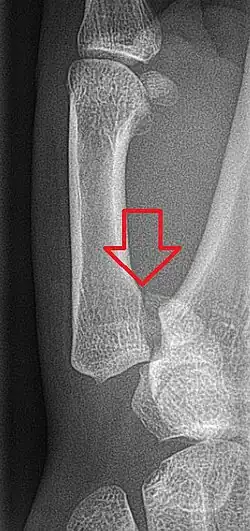

Bennett's fracture or Bennett fracture is a type of partial broken finger involving the base of the thumb, and extends into the carpometacarpal (CMC) joint.[1]

This intra-articular fracture is the most common type of fracture of the thumb, and is nearly always accompanied by some degree of subluxation or frank dislocation of the carpometacarpal joint.

In the case of the Bennett fracture, the proximal metacarpal fragment remains attached to the anterior oblique ligament, which in turn is attached to the tubercle of the trapezium bone of the CMC joint. This ligamentous attachment ensures that the proximal fragment remains in its correct anatomical position.

The distal fragment of the first metacarpal bone possesses the majority of the articular surface of the first CMC joint. Unlike the proximal fracture fragment, strong ligaments and muscle tendons of the hand tend to pull this fragment out of its correct anatomical position.